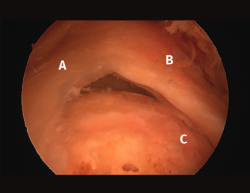

Figura 2. Rotura del manguito rotador en forma de U. A: tendón infraespinoso; B: tendón supraespinoso; C: cabeza humeral.

Figura 5. Rotura de tipo C1. A: rotura pequeña de espesor completo del supraespinoso; B: cabeza humeral.

Sin embargo, las clasificaciones basadas en el tamaño de la rotura deben ser bidimensionales, ya que la visión unidimensional puede ser engañosa, al mostrar el tamaño de la rotura solo desde el plano anteroposterior(4). Por esta razón, proponemos el sistema de clasificación del manguito posterosuperior sugerida por Snyder, que aporta información no solo del tamaño, sino del número de tendones afectados y la presencia de tejido cicatricial(7). En las lesiones de tipo C1 la lesión atraviesa todo el espesor del tendón y en el eje transversal es pequeña y punzante (Figura 5). Las de tipo C2 son roturas de espesor completo pero la distancia entre los extremos de la rotura es menor de 2 cm con escasa retracción (Figura 6). En las de tipo C3 la rotura afecta en sentido transversal entre 3 y 4 cm con mayor retracción implicando 2 tendones (Figura 7). Y las de tipo C4 son la rotura masiva del manguito de los rotadores con una afectación de espesor completo de toda la anchura de 2 o más tendones asociando importante retracción (Figura 8).